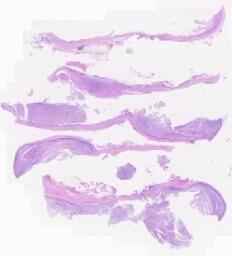

大体所见: 大体:灰白色组织一块,0.6*0.4*0.4cm。

临床资料: 患者,男,66岁,内镜:贲门3-4点可见溃疡,周缘粘膜隆起糜烂,触之易出血。快速幽门螺杆菌检测(强阳)。